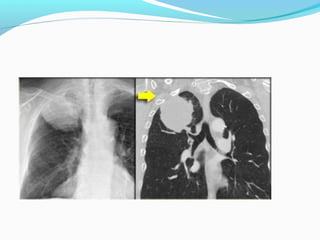

STAGE ??

OPERABLE OR NOT?